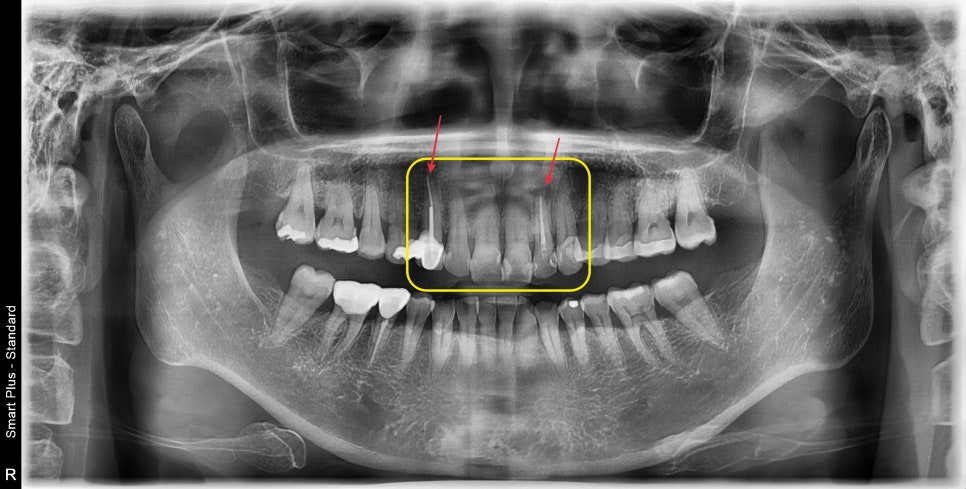

해당 환자분의 치열도 신경치료를 동시에 진행했어야 할 케이스지만

엑스레이를 보았을 때 신경관 내부가 석회화가 진행되어 좁아져 있었습니다.

그래서 신경치료를 안하고 진행이 가능 할수도 있겠구나 라고 생각했습니다.

6개 치아 중 2개는 이미 신경치료가 되어있었고 나머지 4개의 치아의 신경은

신경치료 없이 살려서 지내보면 어떨까 싶었습니다.